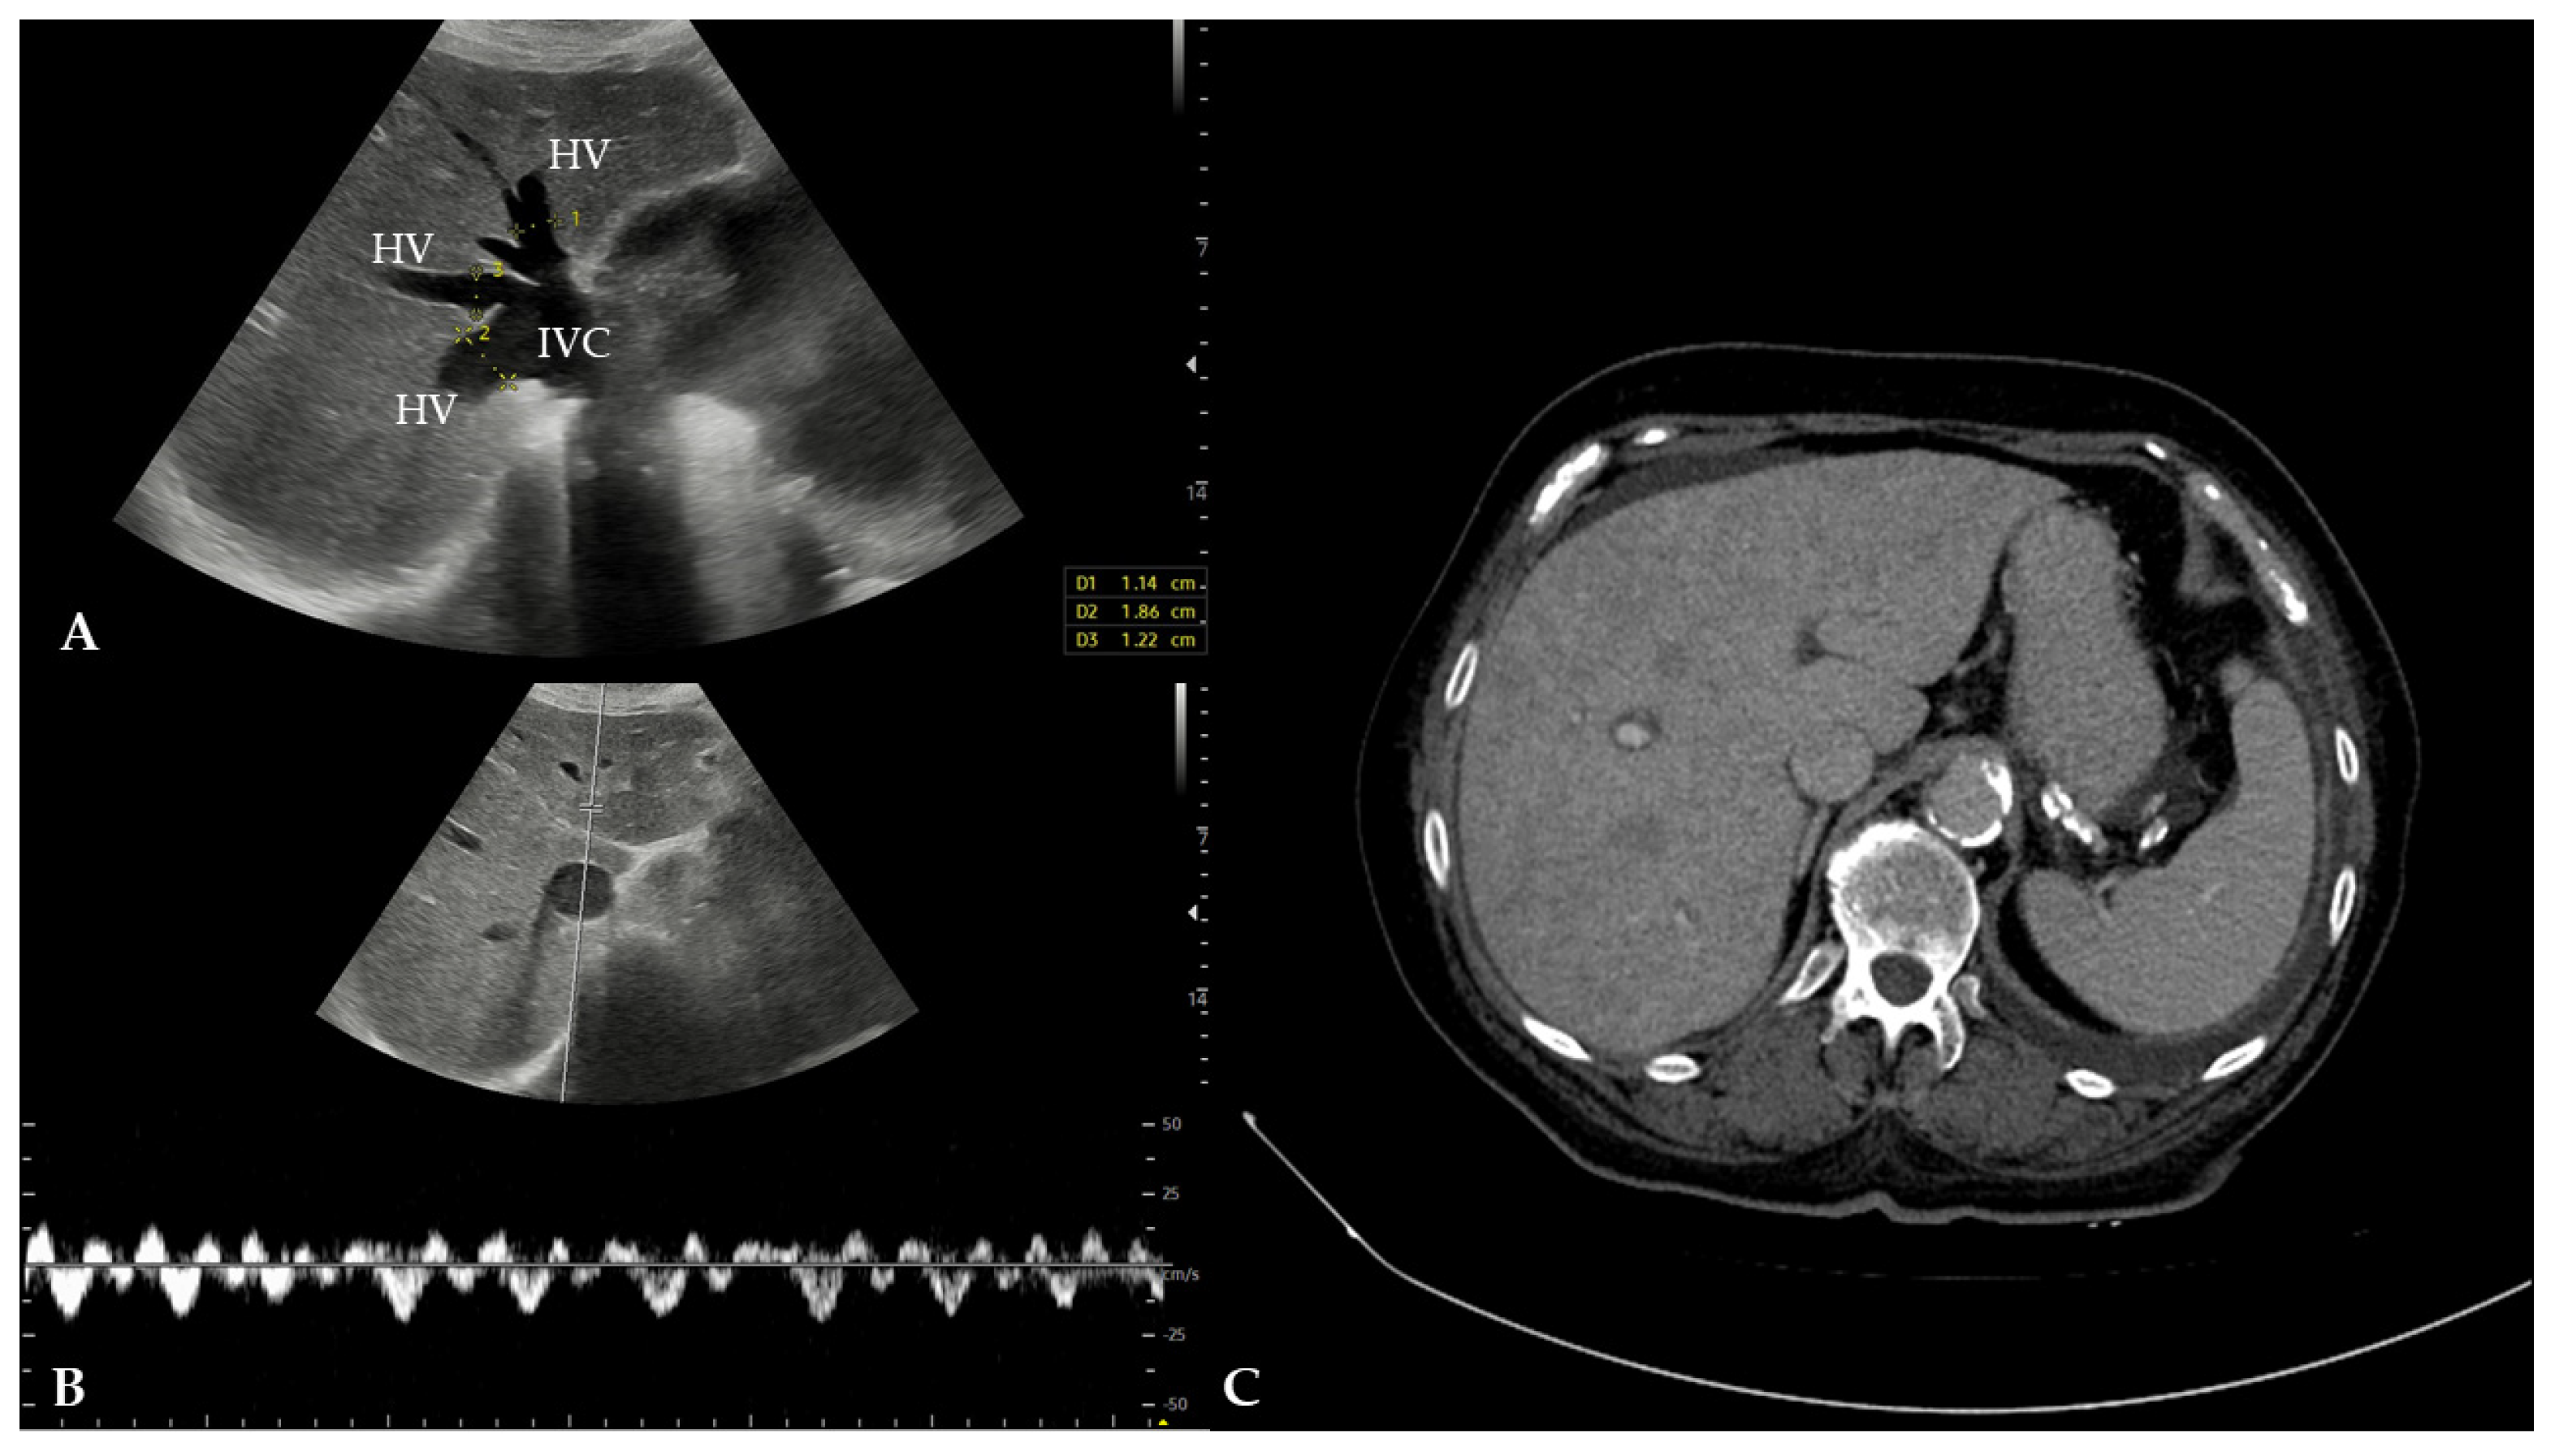

2. Case Presentation